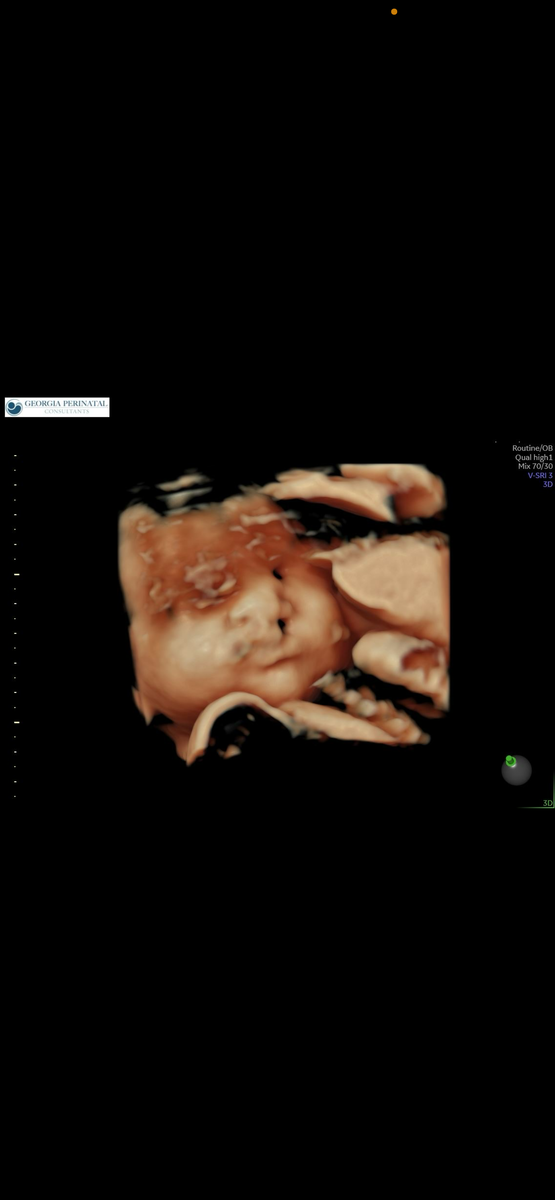

Это пожалуй самый волнующий вопрос. Каждый родитель переживает и пытается представить каким будет малыш. У всех или у многих есть какие то снимки УЗИ. И визуализировать их без насмотренности сложно . Как я и писала группа в face книге помогает . Но она на Английском и не у всех сейчас есть доступ . Ну а пока поделюсь своими. Не знаю почему раньше не сделала .